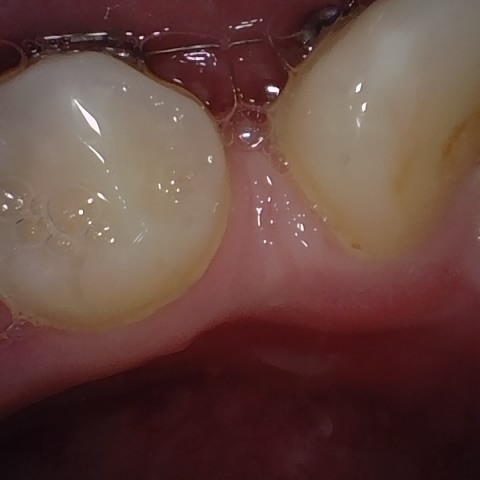

Annotated as "Bad"